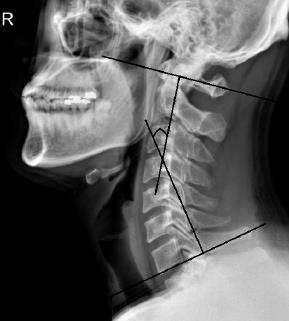

교통 사고시 발생한 채찍 손상으로 경추 주변의 근육이 손상되어서 발생하는 통증이 가장 많지만 그 손상의 정도가 심각할 경우에는 경추의 추체와 추체를 연결하여 고정하는 인대가 손상되어 경추의 불안정을 초래하게 되기도 합니다. 경추의 불안정성을 평가하는 방법은 위와 같이 엑스레이를 찍어보는 것 입니다.

교통사고 후유증은 채찍 손상 혹은 편타성 손상이라 하여 사고로 인한 충격은 목에 엄청난 충격을 주며 이로 인해 목근육의 여러 부분이 긴장됩니다.

이러한 긴장은 목의 경추만곡(목은 약간의 C자 모양의 커브를 이루어야 함)이 감소되어 일자목이 형성되거나 더 지나치게 되면 후만이라고 하여 C자모양이 역전되는 현상이 일어납니다.

일자목과 교통사고 후유증과의 관련성은 연구자마다 상반된 결과를 보입니다. 그러나 채찍손상으로 근육이나 인대의 손상 또는 디스크가 발생되어 근육이 긴장되면 일자목의 발생 가능성은 매우 높아집니다.